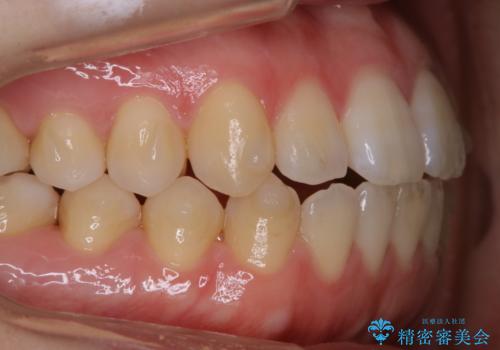

- 歯のホワイトニングを希望されて来院された患者様です。

レーザーを用いたホワイトニングを行いました。

施術前後の変化に大変満足されていました。

薬剤を塗布し、レーザー照射を3セット行いました。